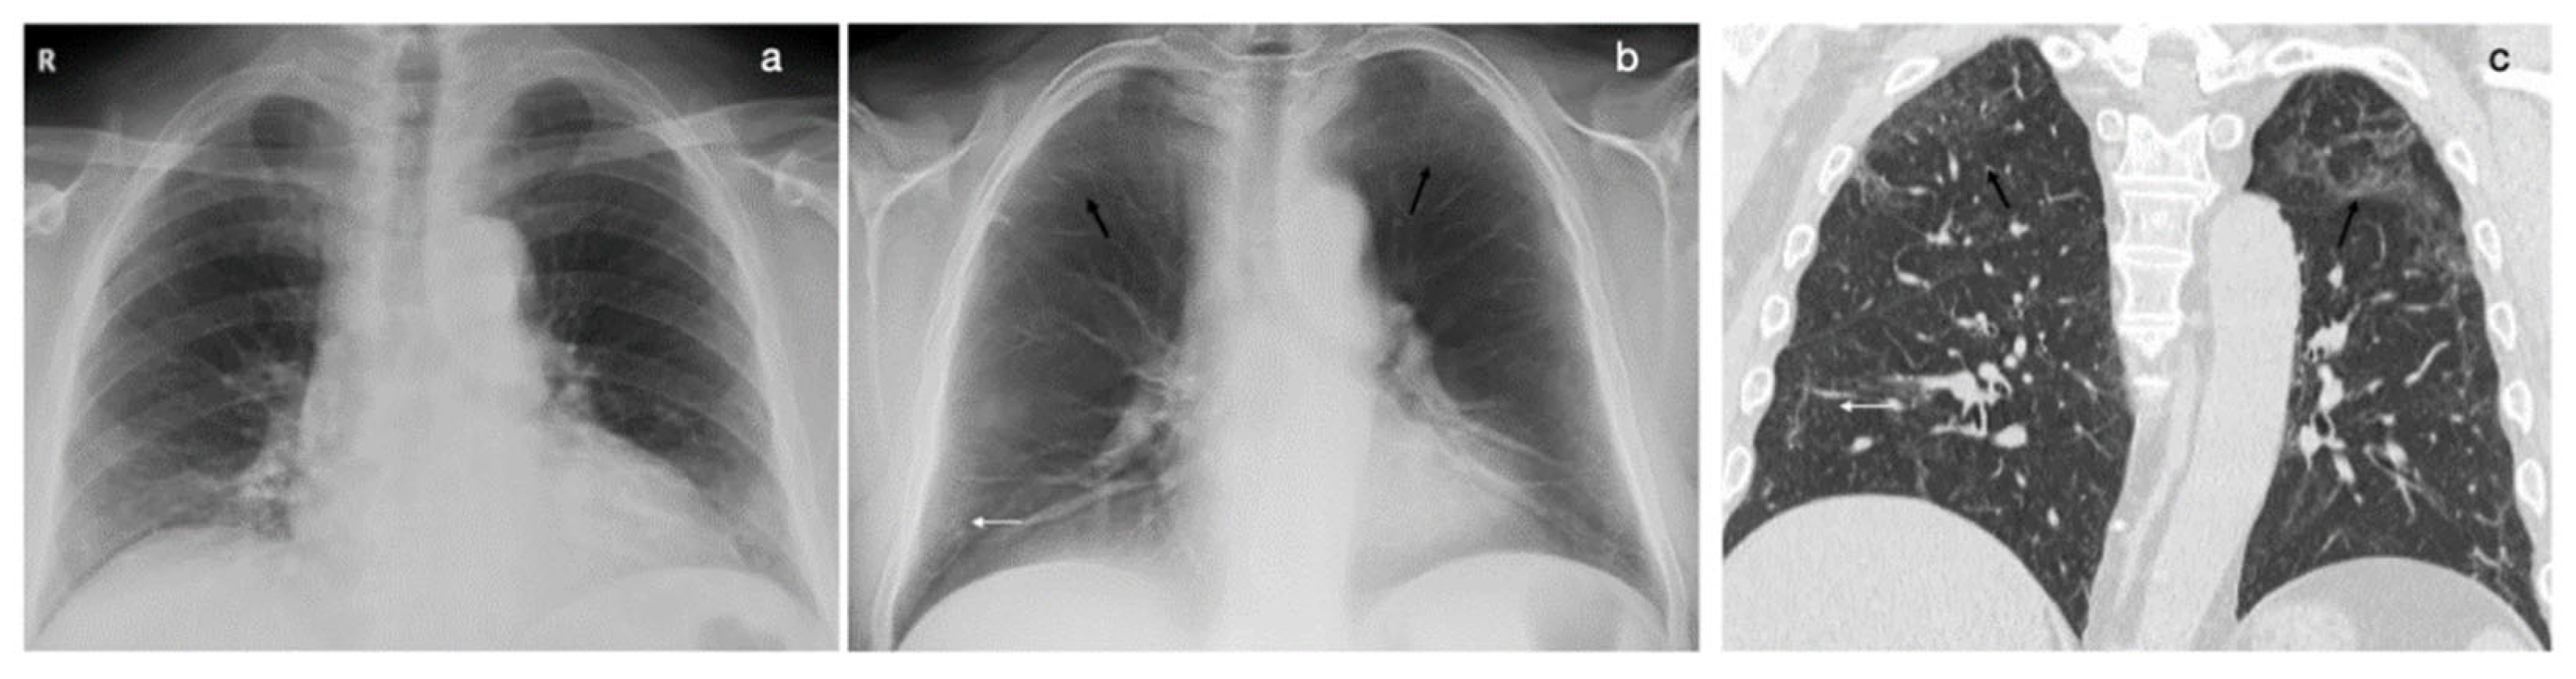

- Kruamak, T.; Edwards, R.; Cheng, S.; Hippe, D.S.; Raghu, G.; Pipavath, S.N.J. Accuracy of Digital Tomosynthesis of the Chest in De-tection of Interstitial Lung Disease Comparison With Digital Chest Radiography. J. Comput. Assist. Tomogr. 2019, 43, 109–114. [Google Scholar] [CrossRef] [PubMed]

- Quaia, E.; Baratella, E.; Cernic, S.; Lorusso, A.; Casagrande, F.; Cioffi, V.; Cova, M.A. Analysis of the impact of digital tomosynthesis on the radiological investigation of pa-tients with suspected pulmonary lesions on chest radiography. Eur. Radiol. 2012, 22, 1912–1922. [Google Scholar] [CrossRef]

- Vult von Steyern, K.; Björkman-Burtscher, I.; Geijer, M. Tomosynthesis in pulmonary cystic fibrosis with comparison to radiog-raphy and computed tomography: A pictorial review. Insights Imaging 2012, 3, 81–89. [Google Scholar] [CrossRef]